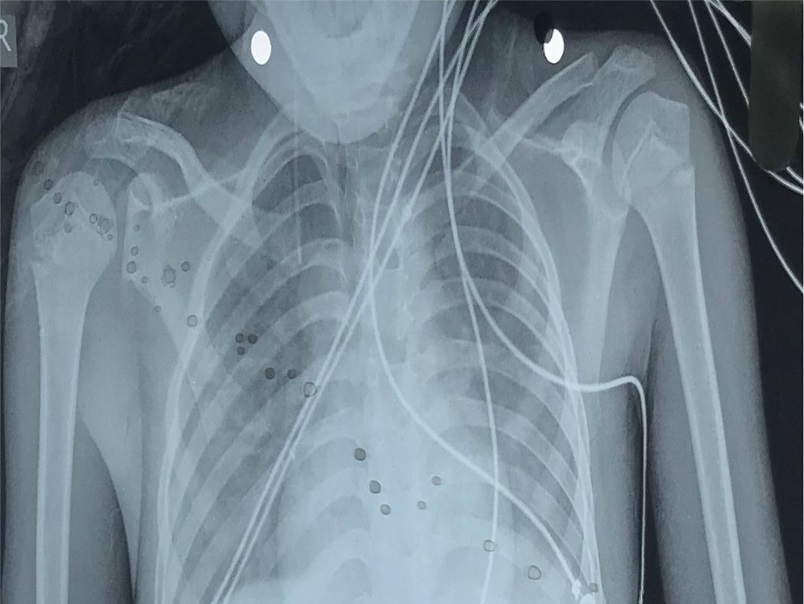

A 12-year-old patient, Aashiq, who entered our hospital

A 12-year-old patient, Aashiq, who entered our hospital in a disoriented state, showing a complex medical condition marked by acute complaints of insidious fever, abdominal pain, altered level of consciousness, inability to speak properly, abnormal b